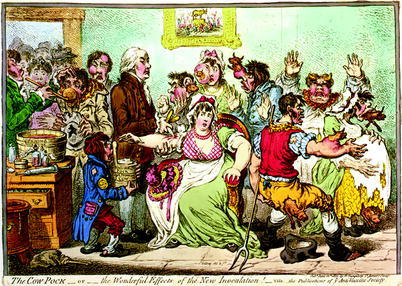

Jenner was not the first to recognize the connection between cowpox and immunity to smallpox. A number of farmers had previously made this observation. For example, Benjamin Jesty, a farmer in Dorset (southern England), had inoculated his wife and children with cowpox material during an outbreak in 1774 and, I assume, induced immunity in the family. In 1796 Jenner tested his hypothesis that the pus from the wounds that occurred on the udder of milking cows contained material that could protect against smallpox by inoculating James Phipps, the son of his gardener, with pus from a wound on the hand of his milkmaid, Sarah Nelmes, who had been infected by a virus from a cow named Blossom. Blossom is probably one of the most famous cows in history, her hide immortalized in St George’s Hospital Medical School in London. James was then variolated with the smallpox virus a number of times and had basically no reaction, showing complete immunity. Jenner then tested vaccination on 23 other people, none of whom came down with smallpox. He presented his data to the Royal Society and published his data [4]. His idea of preventing smallpox with a “vaccine” was not easily accepted on religious grounds (“interfering with the work of God”); also ridiculed was the use of material from a cow (see cartoon, Fig. 1.7) (see Chap. 10.1007/978-3-319-07758-1_19, Vaccines).

Fig. 1.7.

1802 caricature of Jenner vaccinating patients who feared it would make them sprout cow-like appendages. The Cow-Pock—or—the wonderful effects of the new inoculation!—vide. The publications of the anti-vaccine society. Print (color engraving) published June 12, 1802, by H. Humphrey, St James’s Street

In this cartoon, the British satirist James Gillray drew a caricature of a scene at the Smallpox and Inoculation Hospital at St Pancras, showing Edward Jenner administering cowpox vaccine to frightened young women, and cows emerging from different parts of people’s bodies. The cartoon was inspired by the controversy over inoculating against the dreaded disease—smallpox. The inoculation agent, cowpox vaccine, was rumored to have the ability to sprout cow-like appendages. A serene Edward Jenner stands amid the crowd. A boy next to him holds a container labeled “VACCINE POCK hot from ye COW”; papers in the boy’s pocket are labeled “Benefits of the Vaccine.” The tub on the desk next to Jenner is labeled “OPENING MIXTURE,” and bottle next to the tub is labeled “VOMIT.” The painting on the wall depicts worshippers of the Golden Calf. (from Wikipedia).